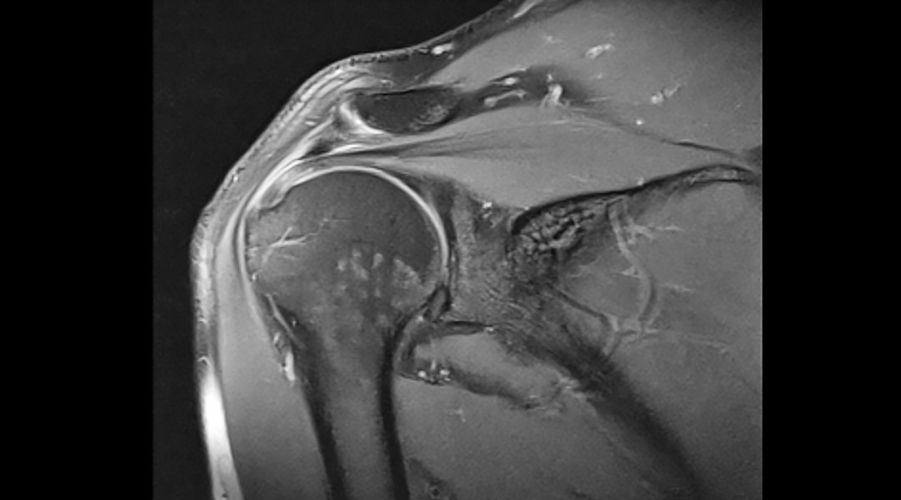

Prof. Dr. Tuluhan Yunus Emre, ortopedi ve travmatoloji alanında uzmanlaşmıştır. Özellikle spor yaralanmaları, diz ve kalça protezleri, omuz cerrahisi, menisküs yırtıkları ve artroskopik cerrahilerde deneyim sahibidir. Hastalarına bireysel odaklı çözümler sunmaktadır.